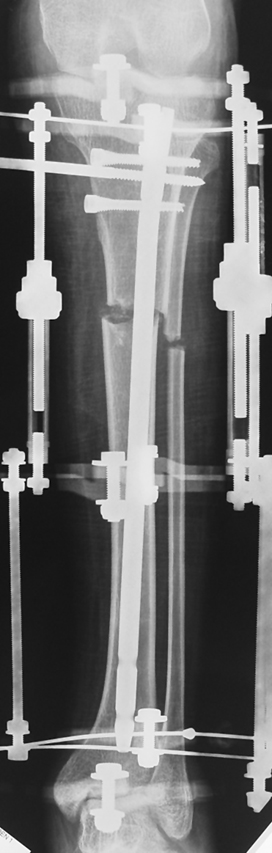

Bu Bacak Kısalık tipi bir kırığın kısalmış pozisyonda kaynaması ile oluşur. Bir çok vaka yetişkinlerde görülür ve sadece bir uzatma ile tedavi edilebilir. Ek deformiteler de aynı anda düzeltilebilir. Bu hastaların çoğu çivi üzerinden uzatma veya tam implante edilen çivi ile tedavi edilebilirler.